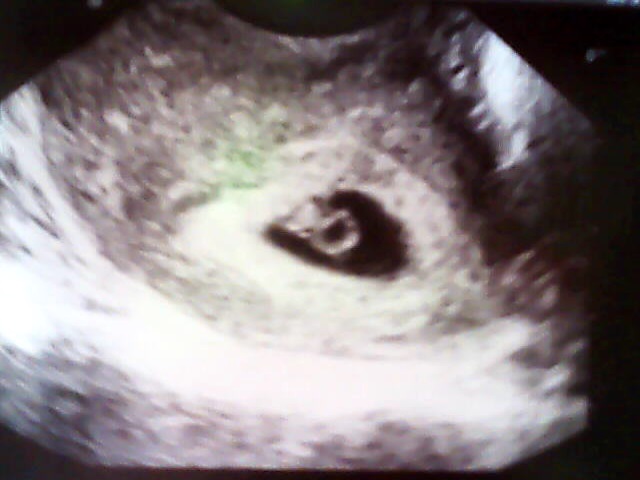

ahojky holky,tak se hlásím,jelikož mě bolelo celkem v podbříšku a navíc jsem nějaká nachlazená skočila jsem si už o týden dříve k doktorovi,aby se mrknul,zda je vše jak má....a naštěstí je vše v pořádku....na dnešním ultrazvuku už byl vidět i plod o velikosti necelých 7mm a dokonce už bilo i srdíčko,takže jsem 6+3 a termín porodu mám podle ultrazvuku 31.10 přesně na 7. narozeniny mého druhého syna,ale i přesto zůstanu v téhle skupině...takže vám všem přeji taky jen pozitivní zprávy a na kontrolu jdu až 23.4 to budu už ve 12 týdnu....přikládám vám sem ultrazvuk z 5+3 a z dneška 6+3....určitě nám to všem dobře dopadne